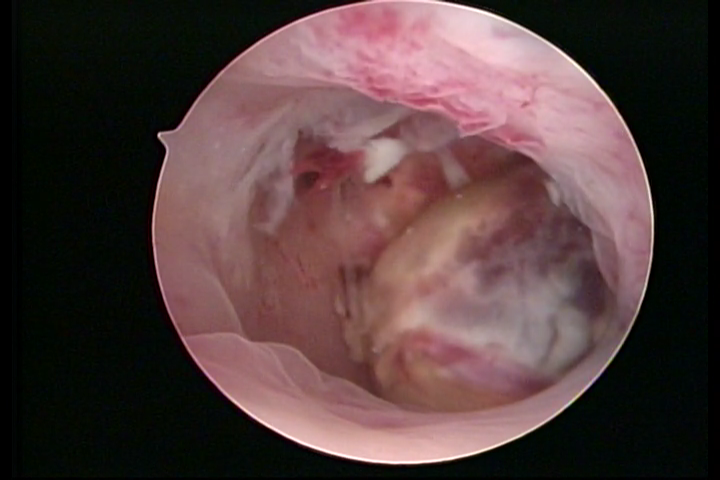

Metaplasia óssea: pontilhado esbranquiçado com calcificações

etaplasia óssea: pontilhado esbranquiçado com calcificações

METAPLASSIA ÓSSEA